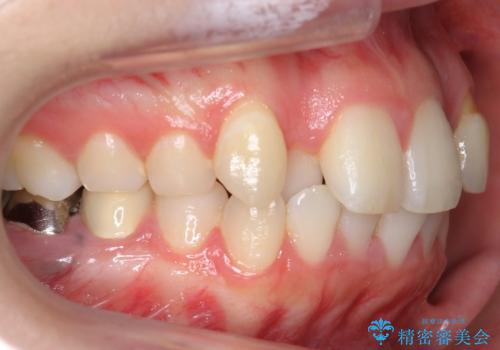

- 前歯のがたつきを主訴に来院。

左上の犬歯が歯肉退縮しており、そこを抜歯して矯正することにしました。

右上については、奥歯をインプラント矯正により後ろに動かして、引っ込んだ前歯を並べるスペースを確保しました。